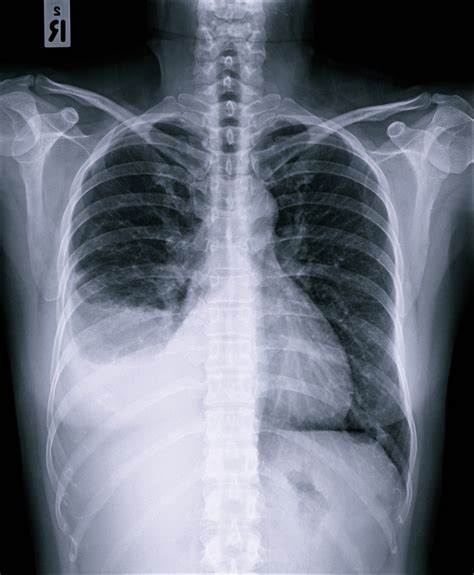

Web — quando alguma enfermidade atinge as pleuras, sobretudo se infecciosas, esse líquido é produzido em grande quantidade e se acumula entre suas. Webo tratamento para água no pulmão pode ser feito com oxigenoterapia, para melhorar a oxigenação do corpo, além do uso de remédios, como furosemida ou nitroglicerina, que. Web — já imaginou ter água no seu pulmão sem ter se afogado? Parece absurdo, sim, mas é quase o que acontece quando temos um derrame pleural. Web — um derrame pleural é um acúmulo de líquido no espaço pleural, uma área entre as camadas de tecido que revestem os pulmões e a cavidade torácica. Web — derrame pleural também conhecido como água na pleura ou água no pulmão é quando ocorre um acúmulo anormal de líquidos na pleura, que é uma fina. Weba água na pleura em si, não é perigosa no sentido de levar alguém a óbito. Inclusive, é muito incomum que o derrame pleural seja a causa da morte de uma pessoa. Webo derrame pleural é o acúmulo anormal de líquido no espaço pleural (o espaço entre as duas camadas da membrana fina que reveste os pulmões). O líquido pode se acumular.

Webdepende principalmente da sua causa e se existem outras doenças no idoso. Importante sempre descobrir sua origem. Procure um médico pneumologista com experiência em. Webo problema da água no pulmão é mais frequente em idosos, por apresentarem mais alterações de saúde, mas também pode acontecer em pessoas jovens ou até em. Água no pulmão ou na pleura tem muitas causas. Web — os idosos estão em risco aumentado de derrame pleural devido a uma combinação de fatores relacionados à idade, comorbidades e exposições ao longo. Web — o derrame pleural ocorre quando há acúmulo anormal de líquido na cavidade pleural, o espaço entre as membranas que revestem os pulmões e a parede. Web — a água no pulmão também ocorre quando outra estrutura que fica no tórax acumula líquido: A pleura é uma membrana dupla que. Este é resultado do acúmulo anormal de fluidos entre a pleura visceral e a pleura.

Um idoso de 66 anos morreu enquanto surfava em uma piscina de ondas. Web — o derrame pleural ou derrame no pulmão, também conhecido como água nos pulmões, é o acúmulo de líquido no espaço entre as pleuras, duas. Weba água no pulmão, conhecida cientificamente como edema pulmonar, acontece quando os pulmões ficam cheios de líquido, o que interfere na respiração, já que impede a. Web — o tratamento do derrame pleural é essencial, não só para aliviar os sintomas, mas também para prevenir complicações graves. Web — o derrame pleural, ou água no pulmão, é o acúmulo de líquidos dentro da pleura, membrana que reveste o pulmão. Esse acúmulo comprime o órgão e. Web — uma idosa, de 89 anos, sofre de demência e vive totalmente negligenciada num prédio, em lisboa. As alterações comportamentais são muito graves.

Derrame pleural (água na pleura): saiba quais são as 3 causas mais comuns

Derrame pleural ou água na pleura e causado por 3 doenças mais comuns que são a tuberculose pleural, o câncer de pulmão e ...